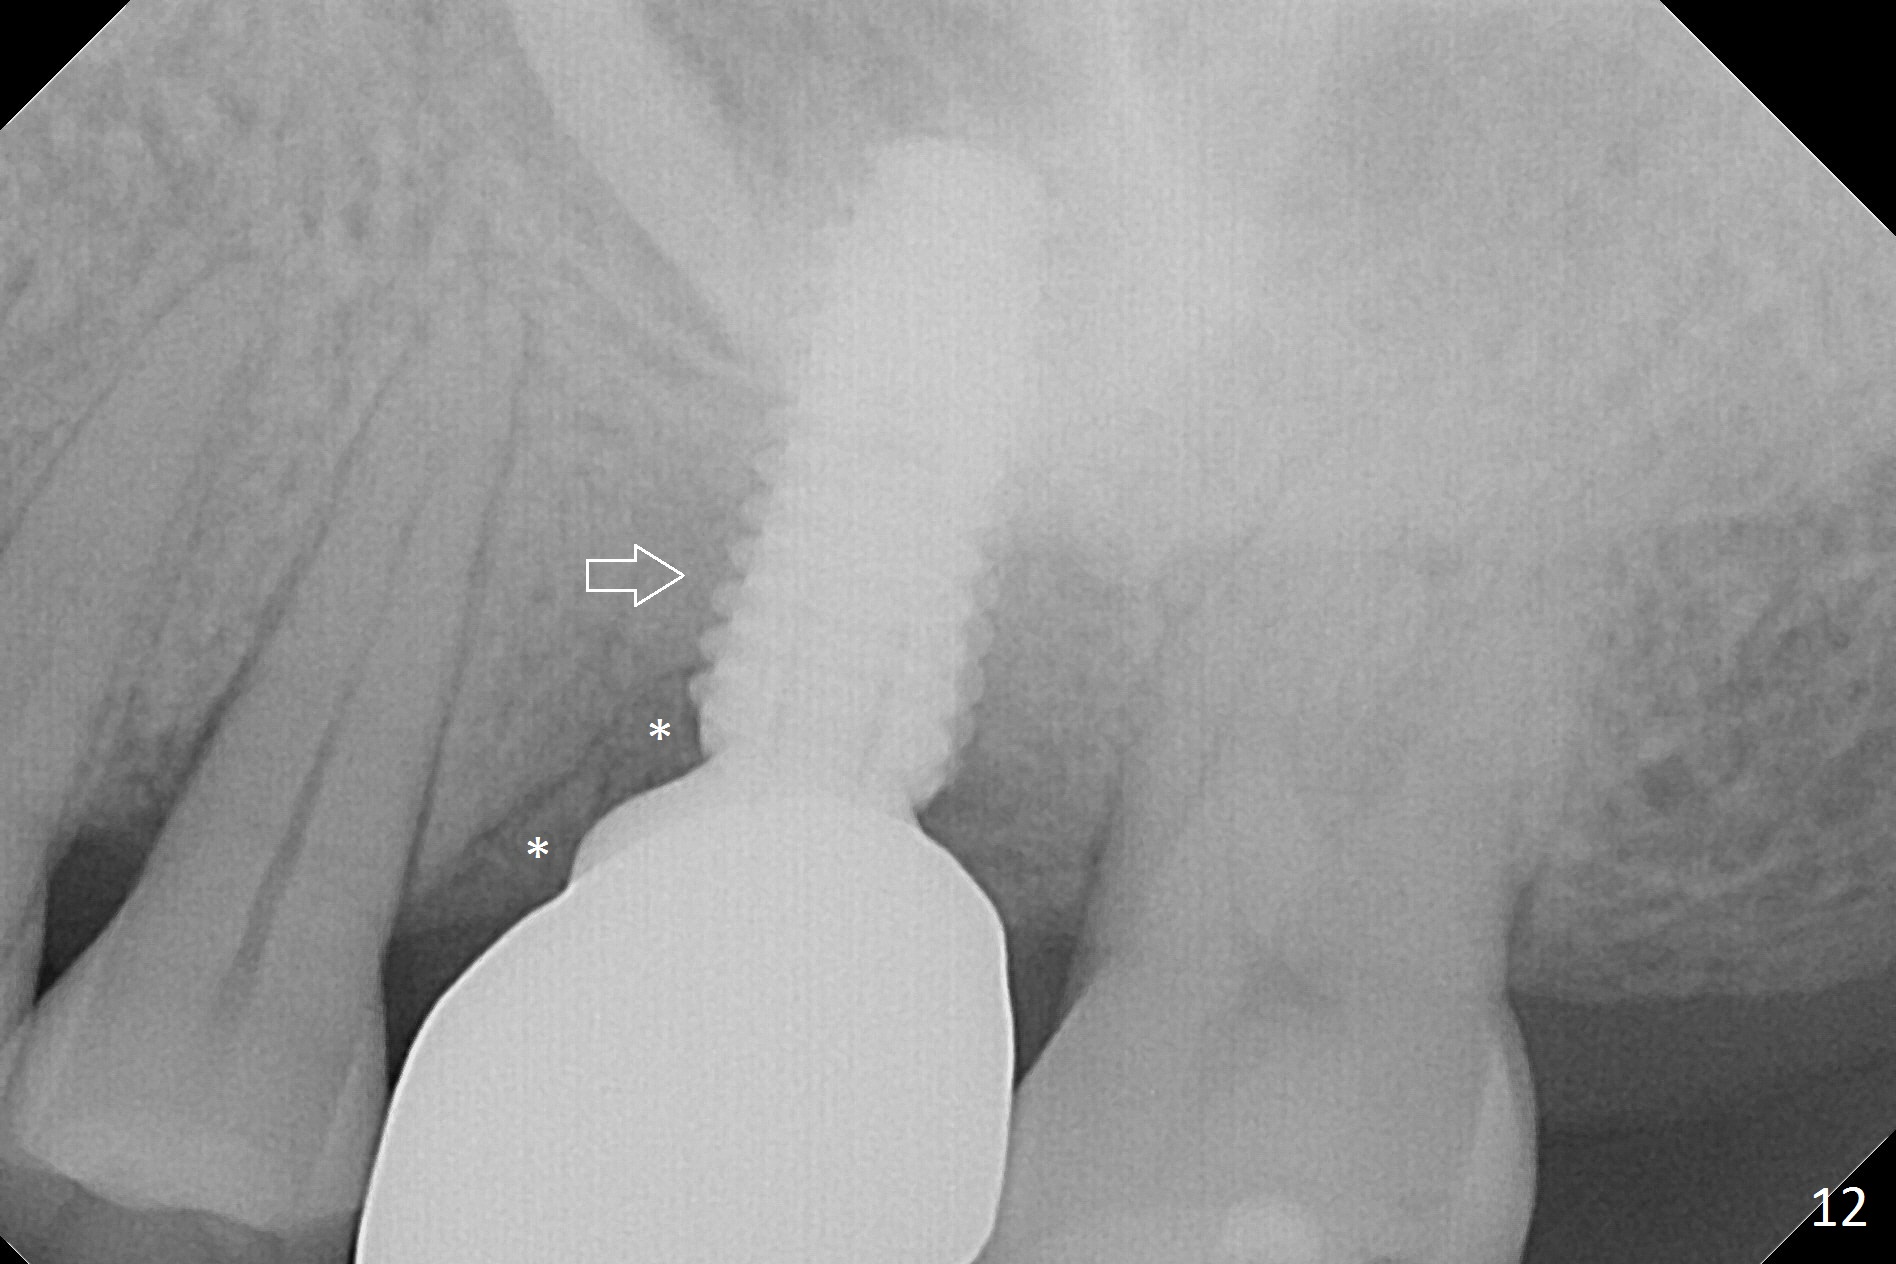

The patient experiences palatal gingival tenderness 5 months post cementation, probably due to loose proximal contacts and excessive use of floss. PA shows new normal bone next to the upper threads (Fig.12 arrow), while new less dense attached to the most coronal threads (*). BWs (Fig.13,14) shows that new bone has grown into the area between the most coronal 2 threads (arrows). When the crown and abutment are removed, the gingiva looks normal except minor laceration buccally. A 7.5x4 mm healing abutment is placed. If the infection resolves, pick up impression will be taken to add porcelain to the proximal surfaces to prevent food impaction.